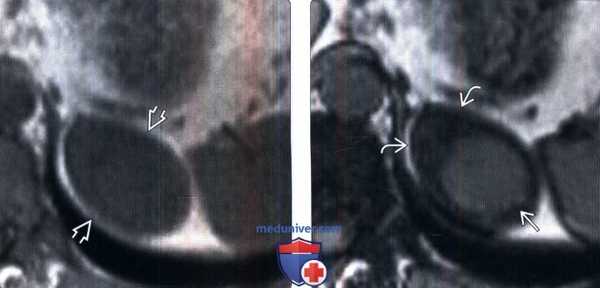

(Слева) МРТ, синфазное Т1-ВИ, аксиальная проекция: выявлено неопределенное поражение левого надпочечника размером 4 см.

(Справа) Соответствующее противофазное изображение показывает, что образование надпочечника фактически состоит из двух отдельных частей. Подавление сигнала от периферической части указывает на аденому с высоким содержанием липидов. Сигнал более высокой интенсивности от центральной части указывает на метастаз. Смешанные опухоли, подобные этим, могут развиваться спонтанно, учитывая высокую распространенность аденом и метастазов у онкологических пациентов.в) Дифференциальная диагностика смешанной опухоли надпочечника: